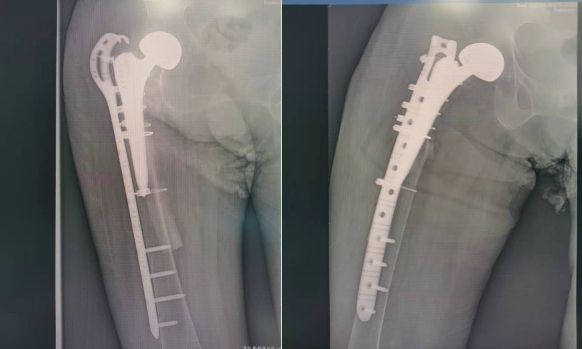

术后X线片